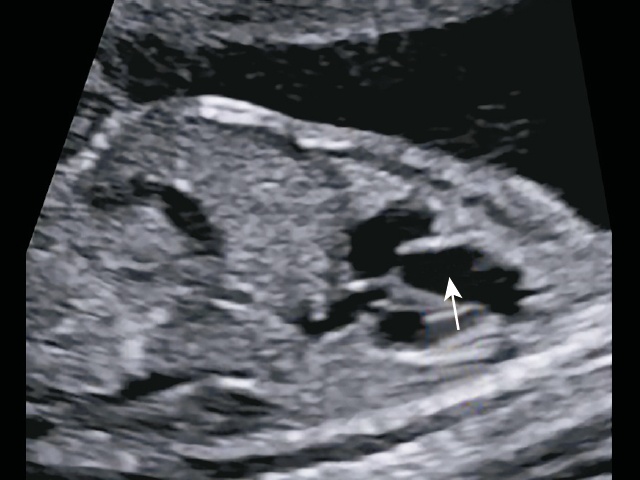

УЗИ в 18 нед: определяем эти 2 сосуда как ОАС, от которого отходит легочная артерия (ошибочно). В режиме ЦДК виден единственный ствол, а ниже желтый допплеровский сигнал - сосуды в привычных нам срезах накладываются друг на друга, предполагаем, что на аорту накладывается боталлов проток с ретроградным кровотоком (рис. 13). Результат ХМА: норма.

а) определяем эти 2 сосуда (см. рис. 12) как общий артериальный ствол, от которого отходит легочная артерия (ошибочно).

б) в режиме ЦДК виден единственный ствол, а ниже желтый допплеровский сигнал - сосуды в привычных нам срезах накладываются друг на друга, предположительно на аорту накладывается боталлов проток с ретроградным кровотоком.